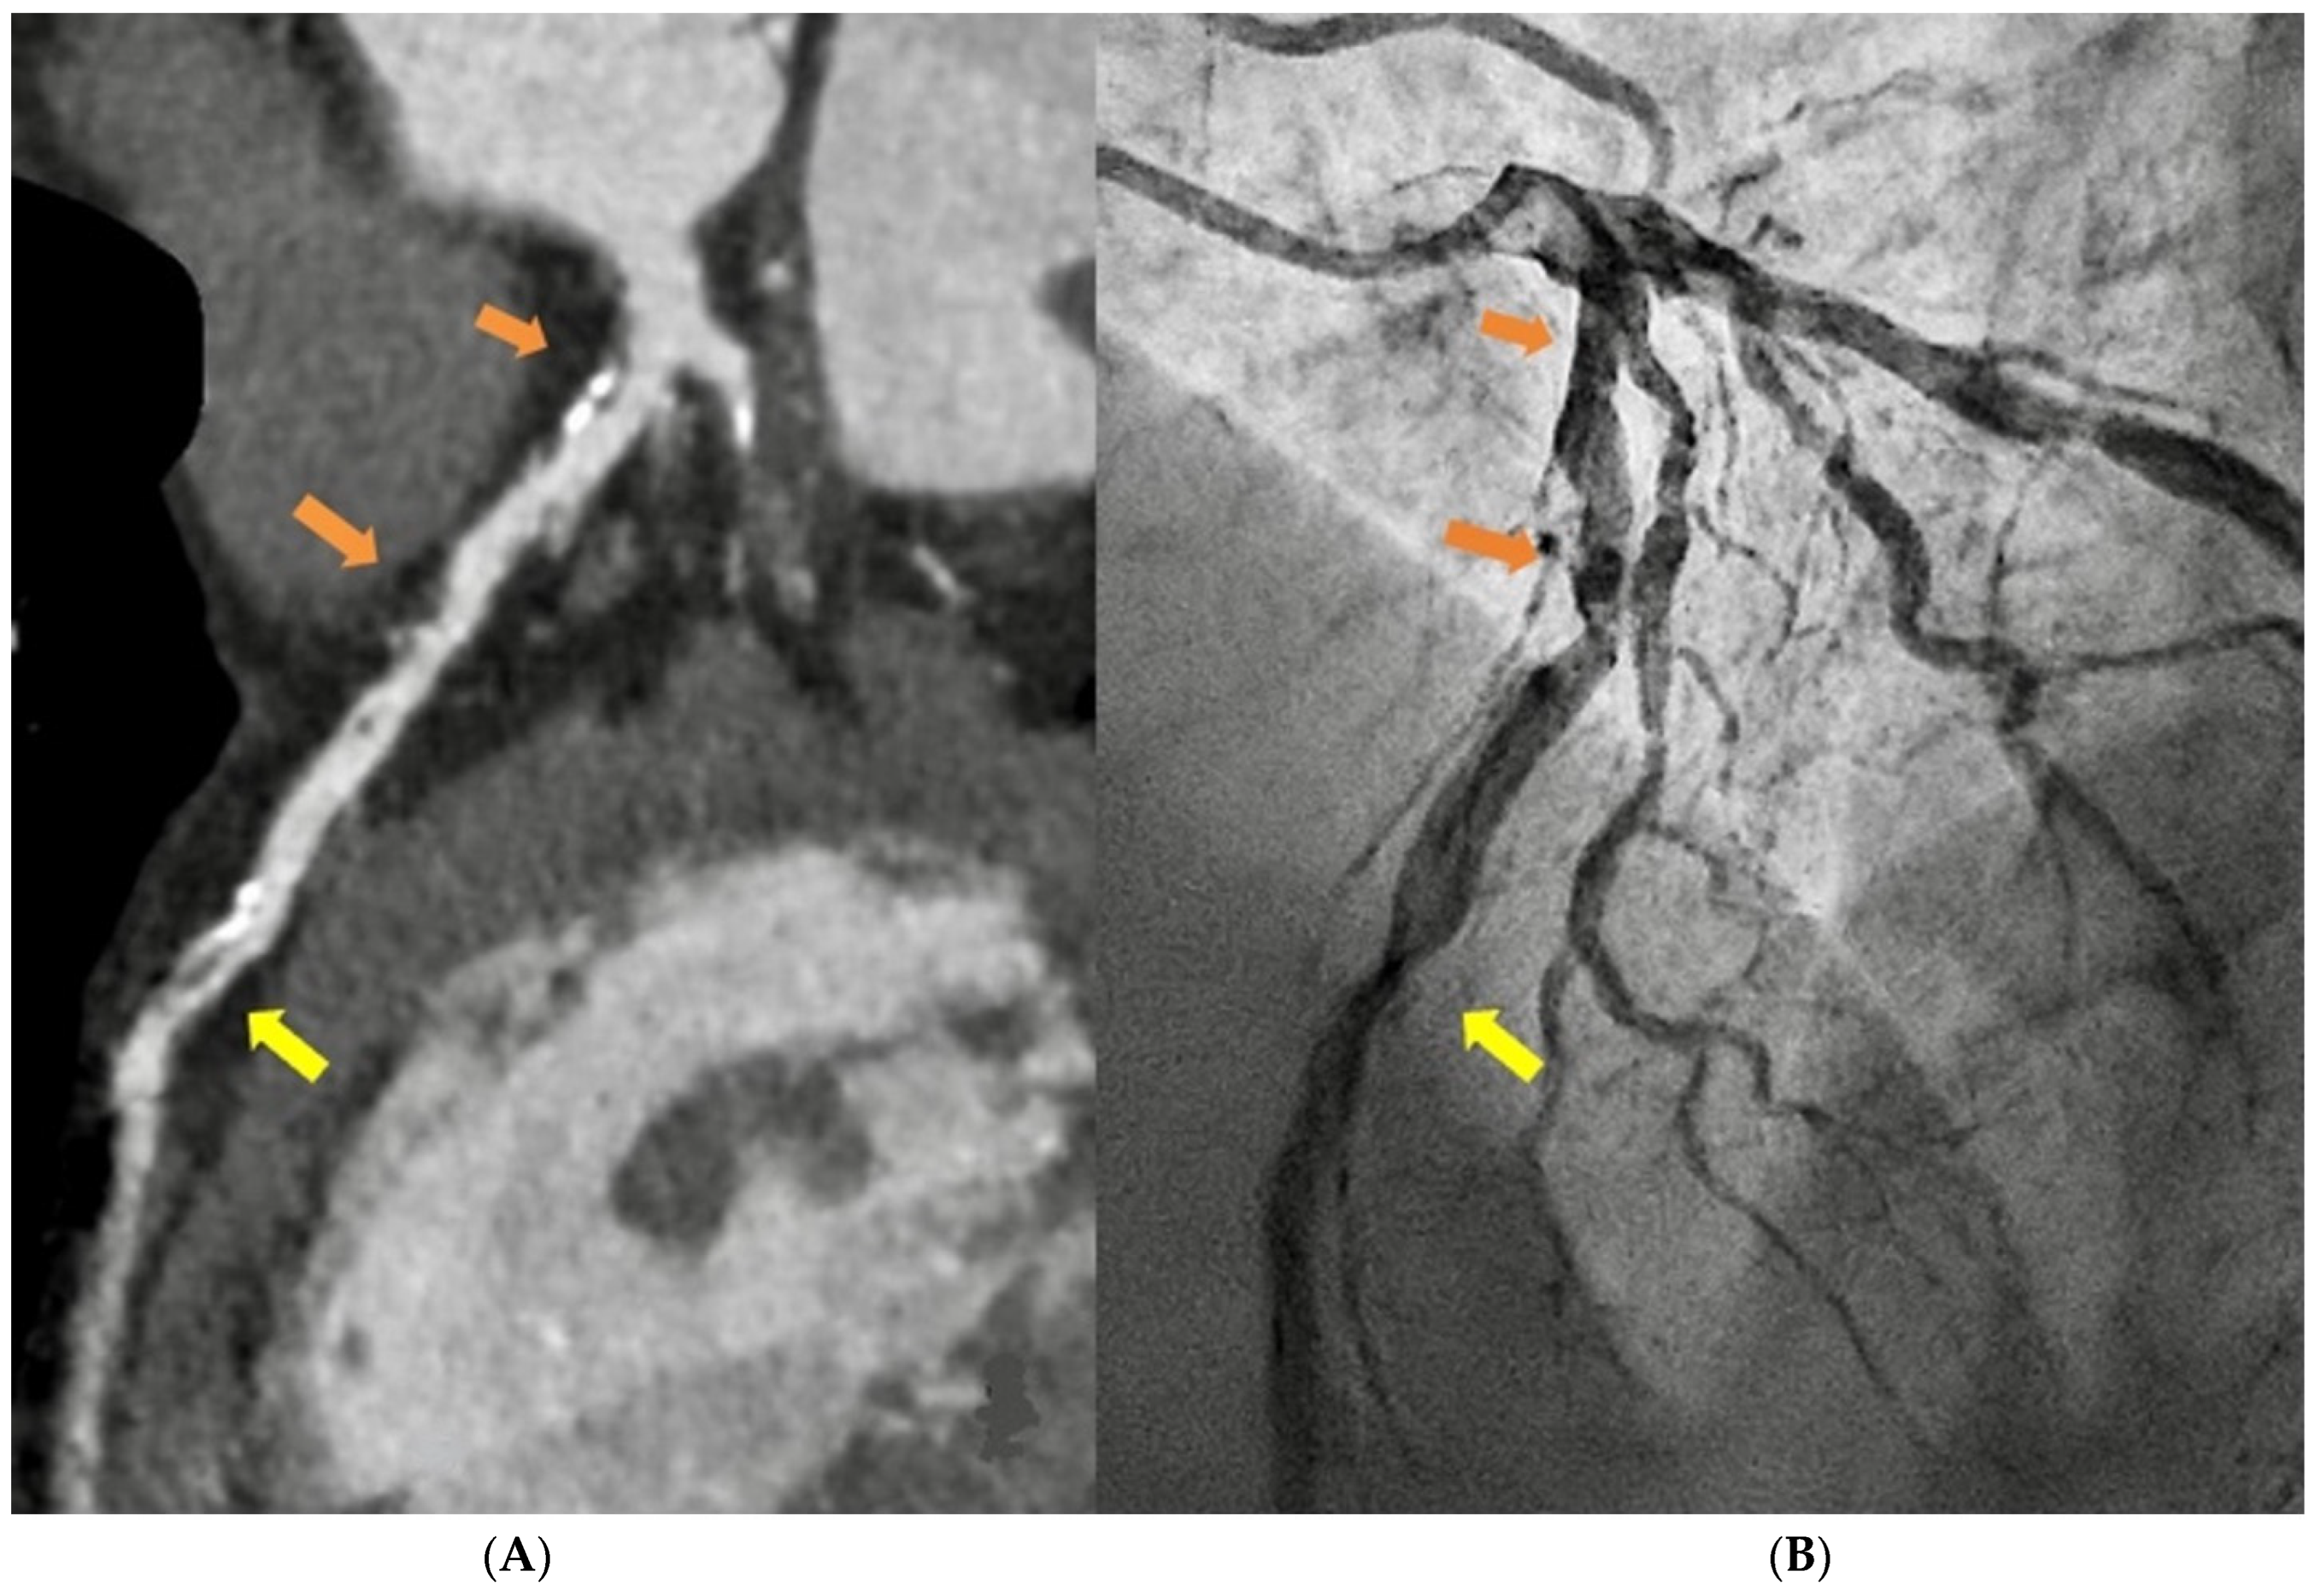

1.1. Computed Tomography